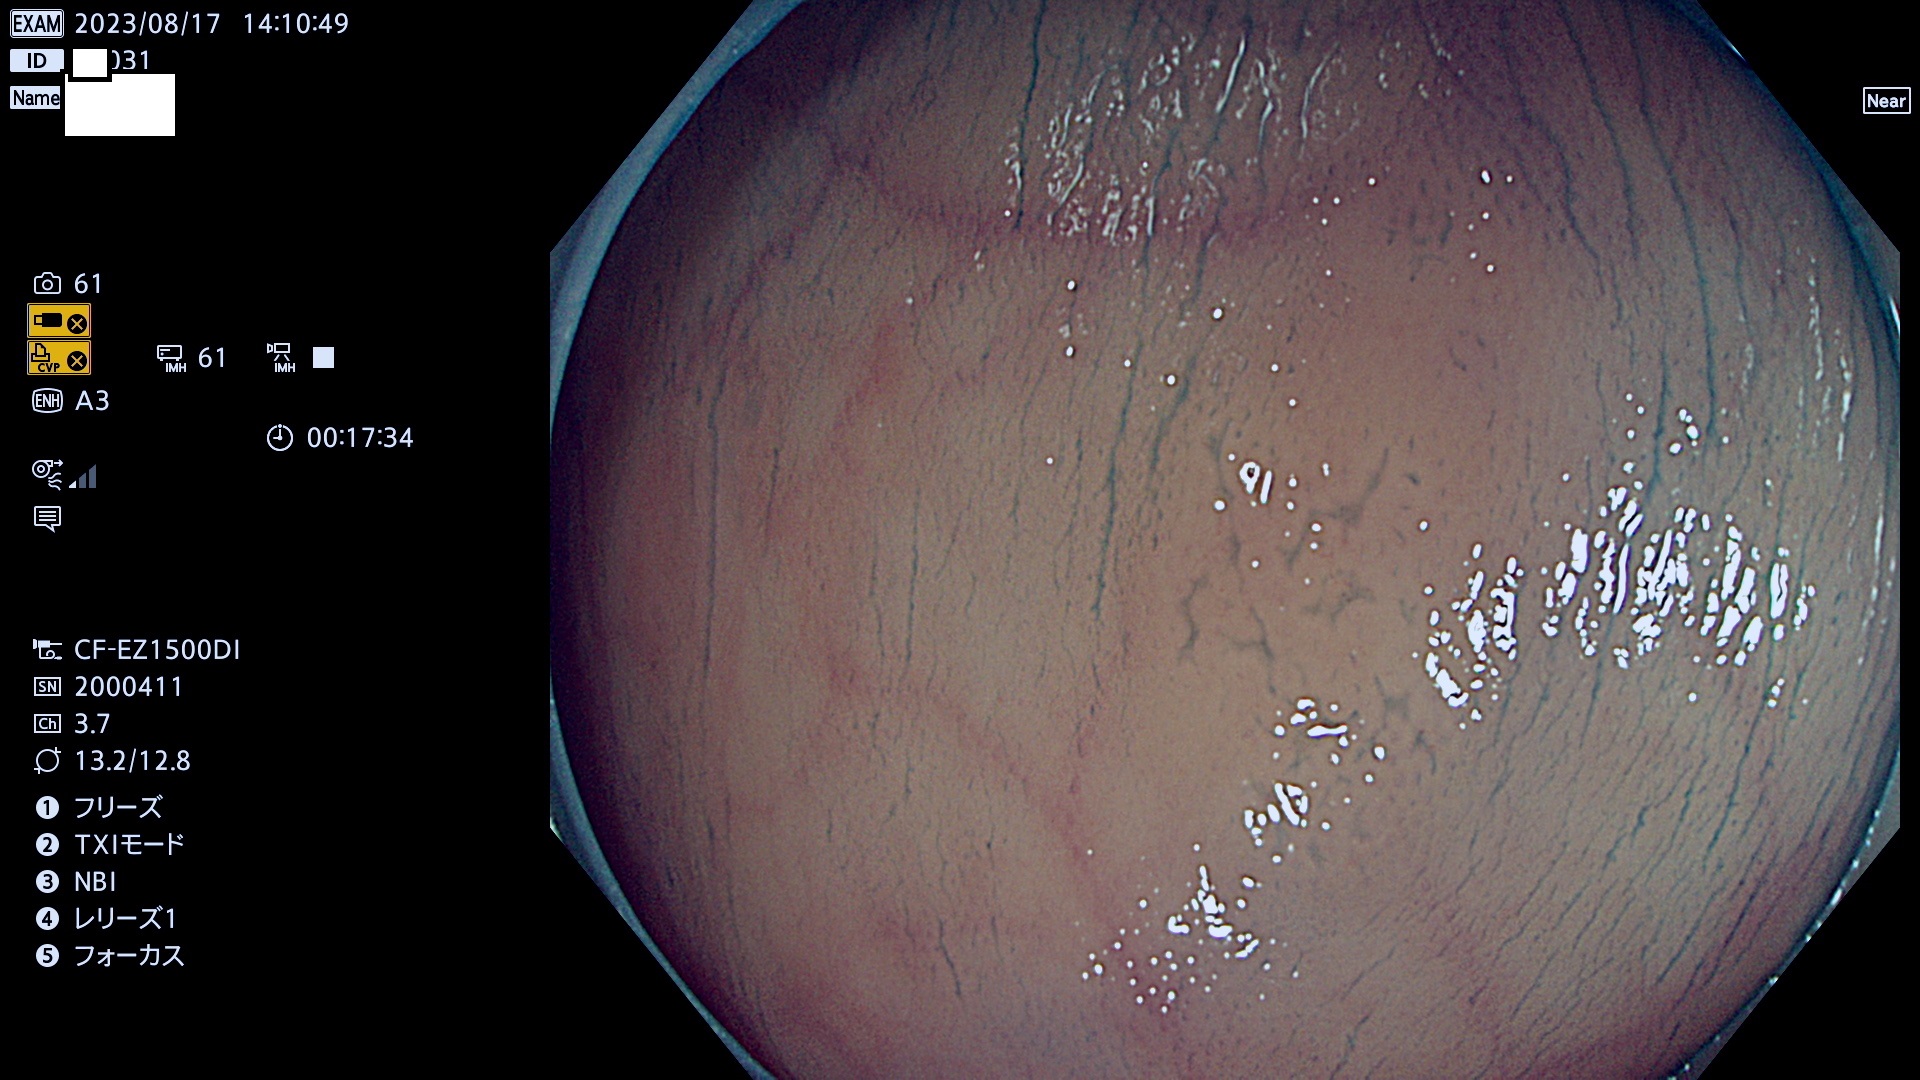

表面型腺腫(Flat Adenoma)の中で、完全に平坦な物をUb、陥凹している物をUcと呼びます。平坦隆起型(Ua)よりも、発見が難しく危険な病変です。このタイプは「内視鏡後・大腸癌の重要犯人」であり、この発見率は「腺腫発見率」よりも、重要な意味があります。

毎週の検査(木・金・土・日)に発見されたUb、Uc型・腺腫を、その週の日曜の夜にUPし1週間、提示します。

抽出の対象期間 2023年8月17日(木)〜8月20(日)の4日間(48件の検査)11件